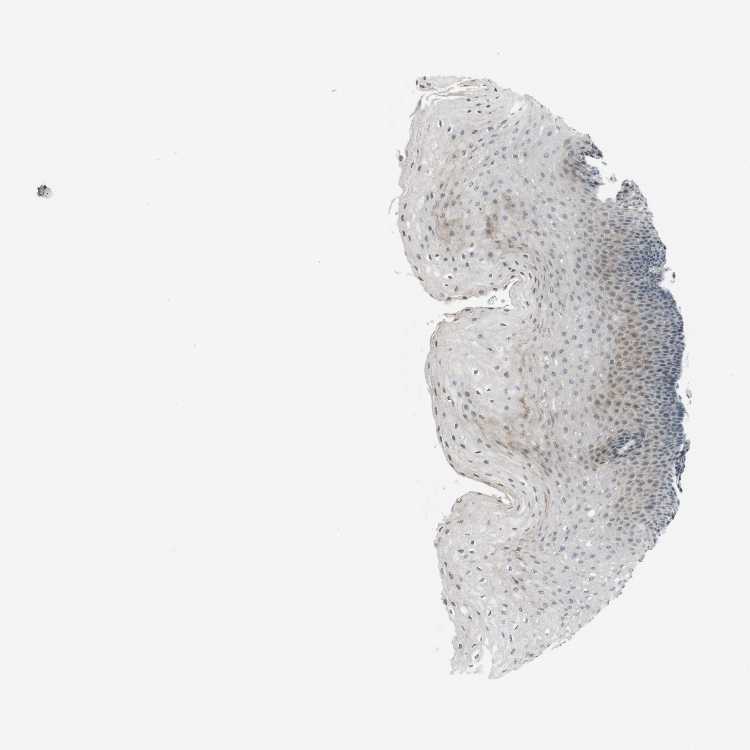

ESOPHAGUS - Antibody stainingi

Antibody staining in the annotated cell types in the current human tissue is reported as not detected, low, medium, or high, based on conventional immunohistochemistry profiling in selected tissues. This score is based on the combination of the staining intensity and fraction of stained cells.

Each image is clickable and will lead to virtual microscopy that enables deeper exploration of all samples and also displays staining intensity scores, fraction scores and subcellular localization as well as patient and tissue information for each sample.

Antibody HPA014484Antibody HPA014485

Squamous epithelial cells Not detectedLow